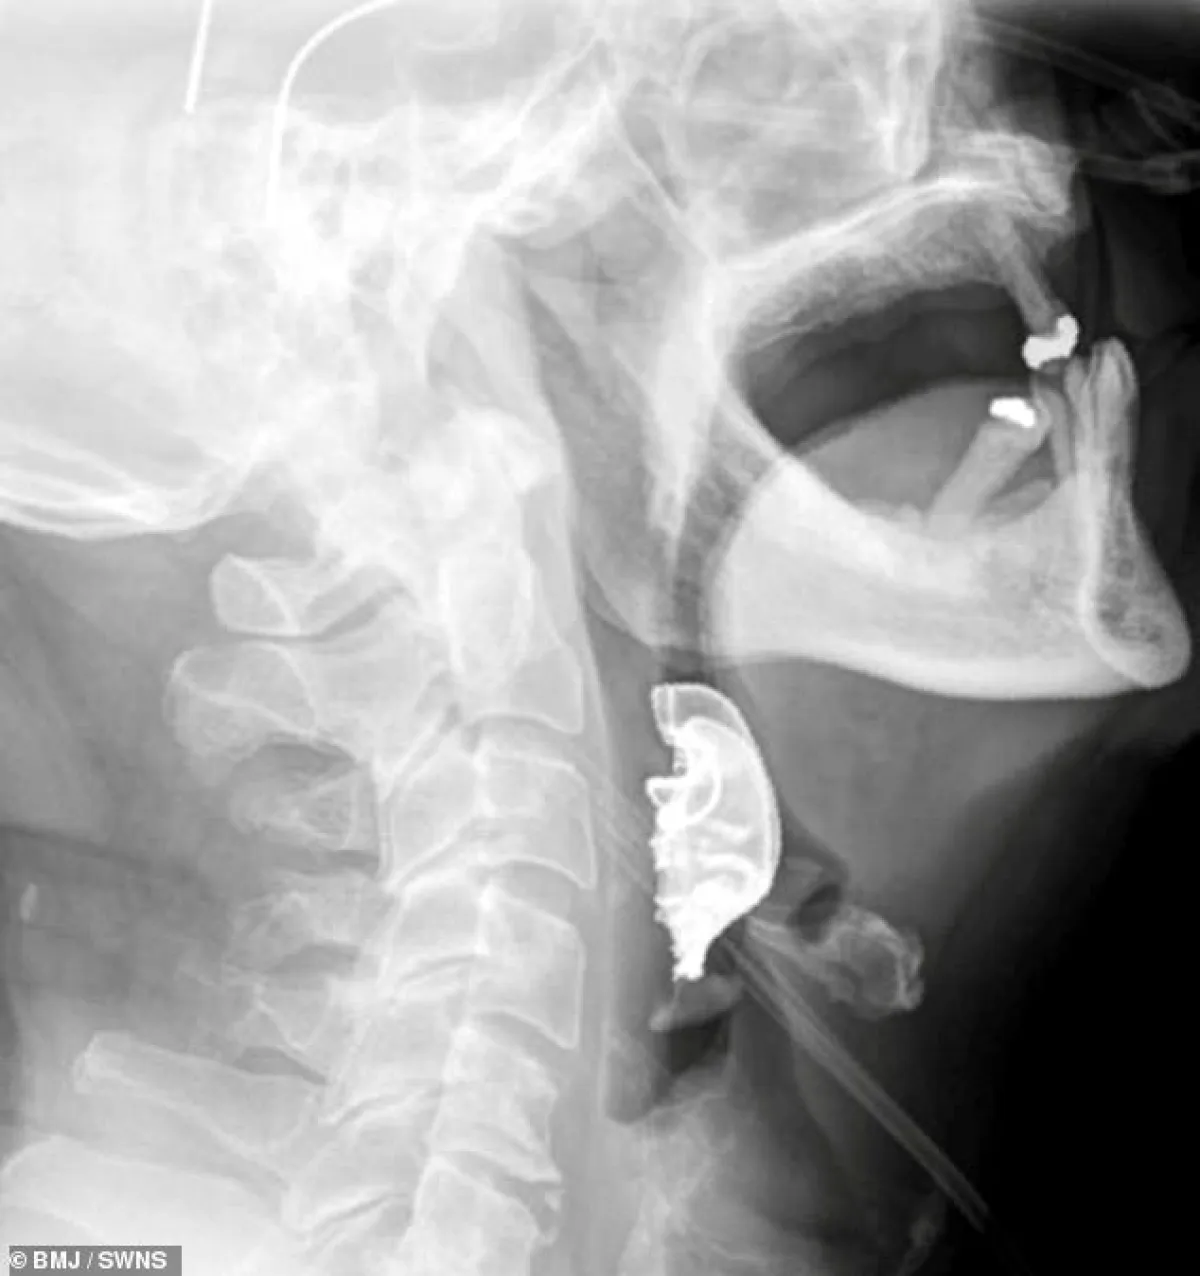

وعندما خضع للفحص، اكتشف الأطباء وجود جسم نصف دائري في حلقه حول الأحبال الصوتية، مما أدى إلى التهابات داخلية، وأثبتت الأشعة الضوئية أن هذا الجسم هو طاقم الأسنان.

وحسب صحيفة "ديلي ميل" البريطانية، و "سكاي نيوز"، فإن الطاقم مكون من شريحة معدنية و3 أسنان أمامية، وقد انحشر في حلق الرجل أثناء جراحة لإزالة ورم حميد من جدار البطن.